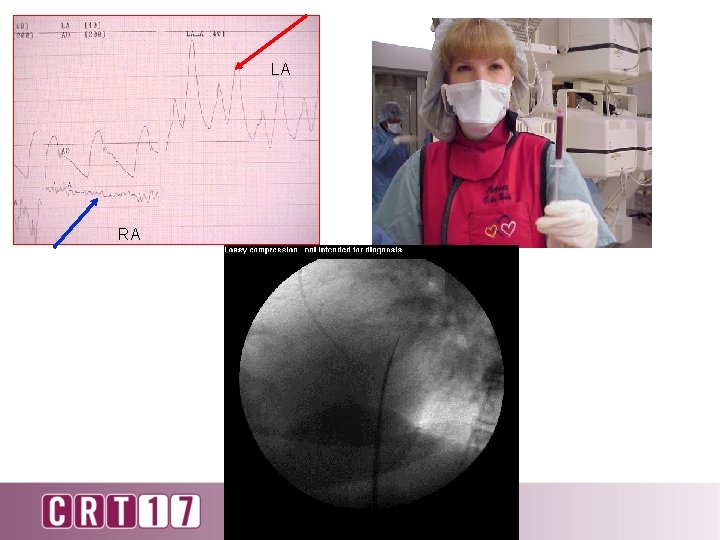

LA RA

STOP – Check needle pressure – Check oxygen saturation – Inject dye